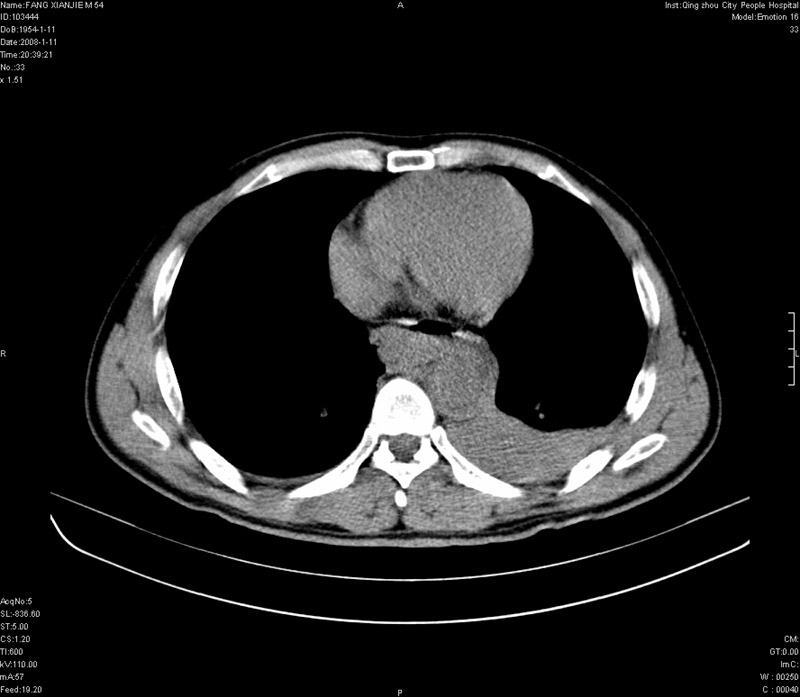

男性,40岁。胸部被车压伤伴胸痛1小时来院就诊。检查:一般情况尚可,血压110/80,胸部及上腹部压痛。结果在三天后公布。骨窗在横断位、冠矢状显示肋骨、胸椎、和胸骨未见骨折征象。

ct11308:胸部外伤1小时(证实病例) (2008-1-13 16:2)结果如下:病人入院后两小时后症状加重,8小时后在征得病人家属同意做了ct增强扫描。如下图。最终临床诊断:外伤性胸主动脉破裂并纵隔内血肿。由于有运动性伪影,胸骨在矢状面重建的图像似有骨折征,这是一种假象,我们称之为“假骨折”,这在多层ct重建中经常性遇到,必要时要结合横断图像鉴别之。现在,病人的一般情况较差,是否要手术家属尚有争议,如果手术修补,难度较大,需要专门预定制作固定支架。

当然,对于该病例,其它非重要的诊断还有:右侧少量气胸;左侧胸腔积液;左侧轻度肺挫裂伤。对于纵隔内血肿,我们曾经遇到过多例,也有怀疑主动脉的破裂,但是,均未得到具体出血部位的明确诊断。